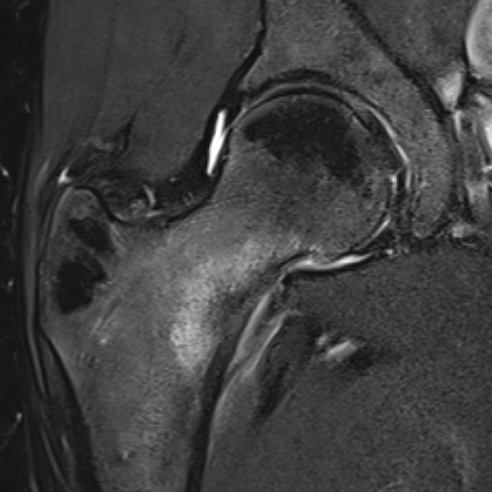

3. Femoral neck stress fracture